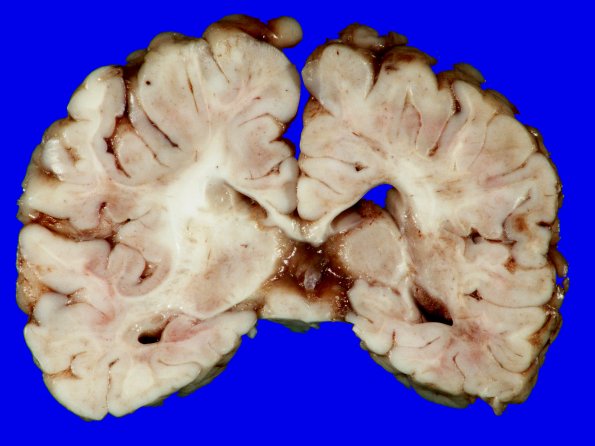

Washington University Experience | VASCULAR | Ulegyria | 10B6 Hypoxia-Ischemia, neonatal (ulegyria) (Case 10) Gross_9

There are numerous examples of ulegyria, white matter loss and dilated ventricles in the caudal brain slices.